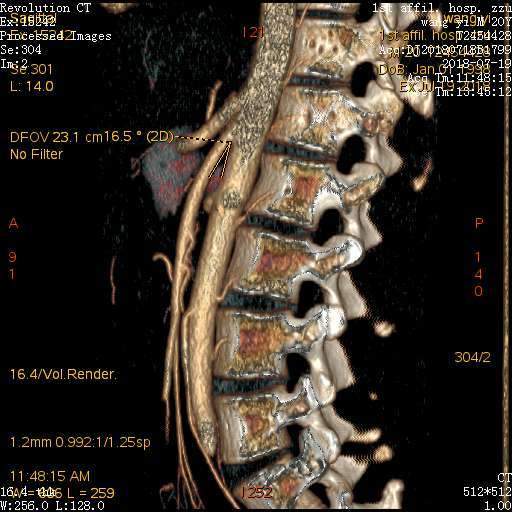

肠系膜上动脉压迫综合征良性十二指肠瘀滞症

图片尺寸512x512